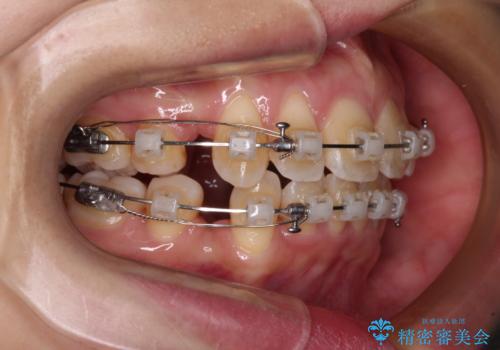

- クリアブラケット

口元を積極的に引っ込めるために、上下左右の小臼歯4本を抜歯し、目立たないワイヤー装置にて矯正治療を行うこととしました。

上下前歯の歯軸の角度が大きく改善され、お口を閉じたときに顎先に認められた梅干し様の皺も改善されました。